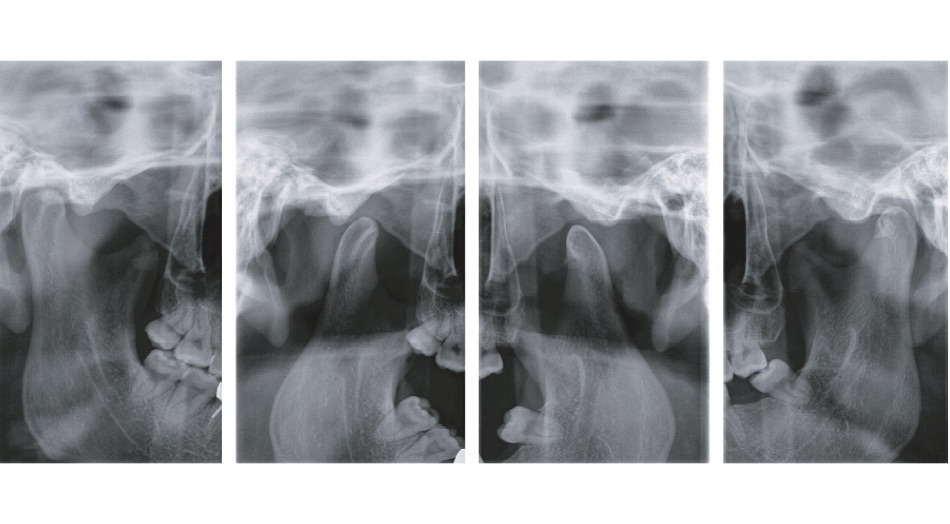

顎関節の観察

顎関節側方二重撮影